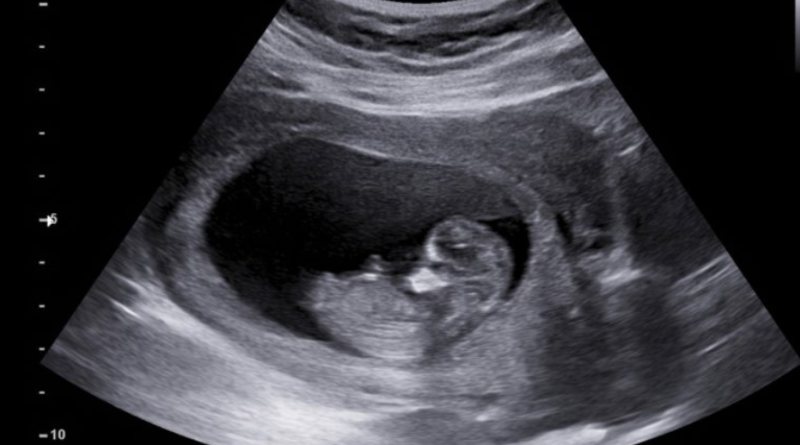

The study – the first of its kind, in which researchers have conducted extensive metabolic profiling and measured PFAS in human foetuses – was published in the scientific journal Lancet Planetary Health on Monday (8 January). It found that foetuses exposed to PFAS have altered metabolism and liver function even before birth, which may increase the risk of metabolic diseases, such as diabetes, in adulthood.

A team of researchers from Örebro University and the University of Aberdeen studied 78 foetuses that were voluntarily aborted between weeks 12 and 19 and considered essentially healthy.

“We found PFAS in the livers of the fetuses, and unfortunately, the results provide strong evidence that exposure to these forever chemicals in the womb affects the unborn child,” said Paul Fowler from the University of Aberdeen, who co-led the study.

“Those exposed to higher levels of PFAS have altered metabolism and liver function long before birth,” he added.

Cover photo: The likely impact of PFAS is similar to the changes that occur as a result of metabolic diseases like diabetes and fatty liver. [SHUTTERSTOCK/AePatt Journey]